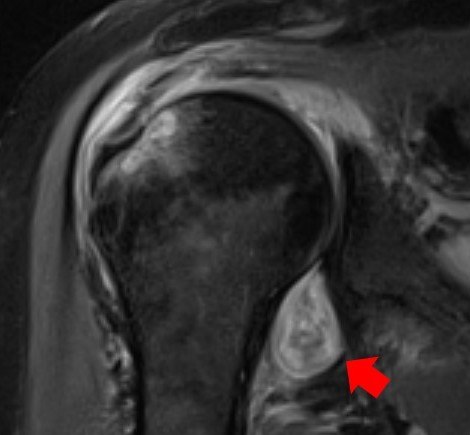

U większości pacjentów chorujących na Covid-19 bóle mięśni i stawów szybko mijają. Jest jednak grupa chorych, u których objawy na przykład reumatoidalnego zapalenia stawów, czy zapalenia mięśni są bardziej poważne i utrzymują się dłużej. Naukowcy z Northwestern Medicine po raz pierwszy potwierdzili te objawy z pomocą obrazów wykonanych techniką magnetycznego rezonansu jądrowego (NMR). W swojej publikacji opisują przypadki pacjentów hospitalizowanych w Northwestern Memorial Hospital z powodu Covid-19 w okresie od maja do grudnia 2020 roku.

Przekonaliśmy się, że Covid-19 może sprowokować reakcję oganizmu przeciwko sobie na różne sposoby, w tym prowadzący do reumatoidalnego zapalenia stawów, które potem będzie wymagało już ciągłej terapii - mówi współautorka pracy, radiolog, dr Swati Deshmukh. U wielu pacjentów objawy kostno-szkieletowe ustępują, ale są tacy, u których są poważniejsze i prowadzą do poważnego pogorszenia jakości życia. Nowoczesne metody obrazowania pokazują nam, czy bóle stawów i mięśni są podobne do tych, które odczuwamy w grypie, czy stoi za nimi znacznie bardziej podstępny mechanizm.

Naukowcy z Northwestern Medicine zwracają uwagę na to, że nowoczesne metody diagnostyczne, w tym obrazowanie z pomocą Magnetycznego Rezonansu Jądrowego, tomografia komputerowa, czy ultrasonografia mogą pomóc zdiagnozować długotrwałe objawy Covid-19 nawet u osób, które wcześniej nie wiedziały, że przeszły zakażenie koronawirusem. To przyspieszy zastosowanie terapii, które mogą te objawy złagodzić. Taka diagnostyka, wykazująca obecność stanów zapalnych, obrzęków, czy nawet obszarów martwicy może też pomóc w ocenie, czy do uszkodzenia doszło w wyniku bezpośredniego działanie wirusa, czy w rezultacie sprowokowanej przez niego odpowiedzi autoimmunologicznej.